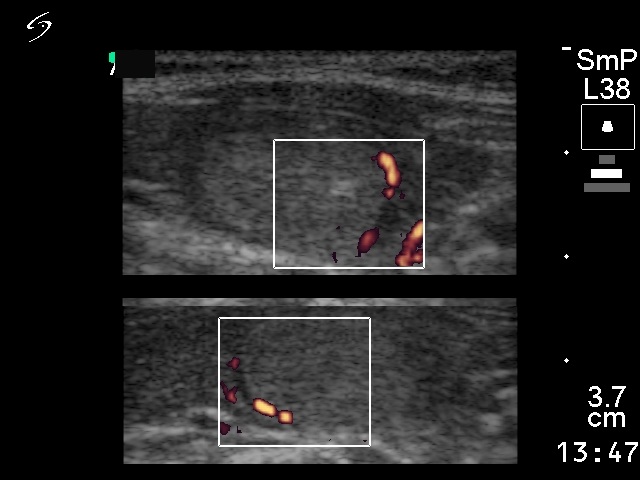

Follicular adenoma - Case 25. |

Ultrasonography: a solitary echonormal nodule within the moderately hypoechogenic left lobe.

Histopathology: microfollicular adenoma and focal lymphocytic thyroiditis.

Comment: in our practice with more than 42,000 FNACs only 5 patients occurred who had carcinoma in an echonormal nodule. Nevertheless, the echo structure of a nodule is influenced by the surrounding normal parenchyma. So, the significance of an echonormal nodule in the case of an underlying Hashimoto thyroiditis (hypoechogenic thyroid) differs from that observed in a patient without thyroiditis, i.e. echonormal thyroid.